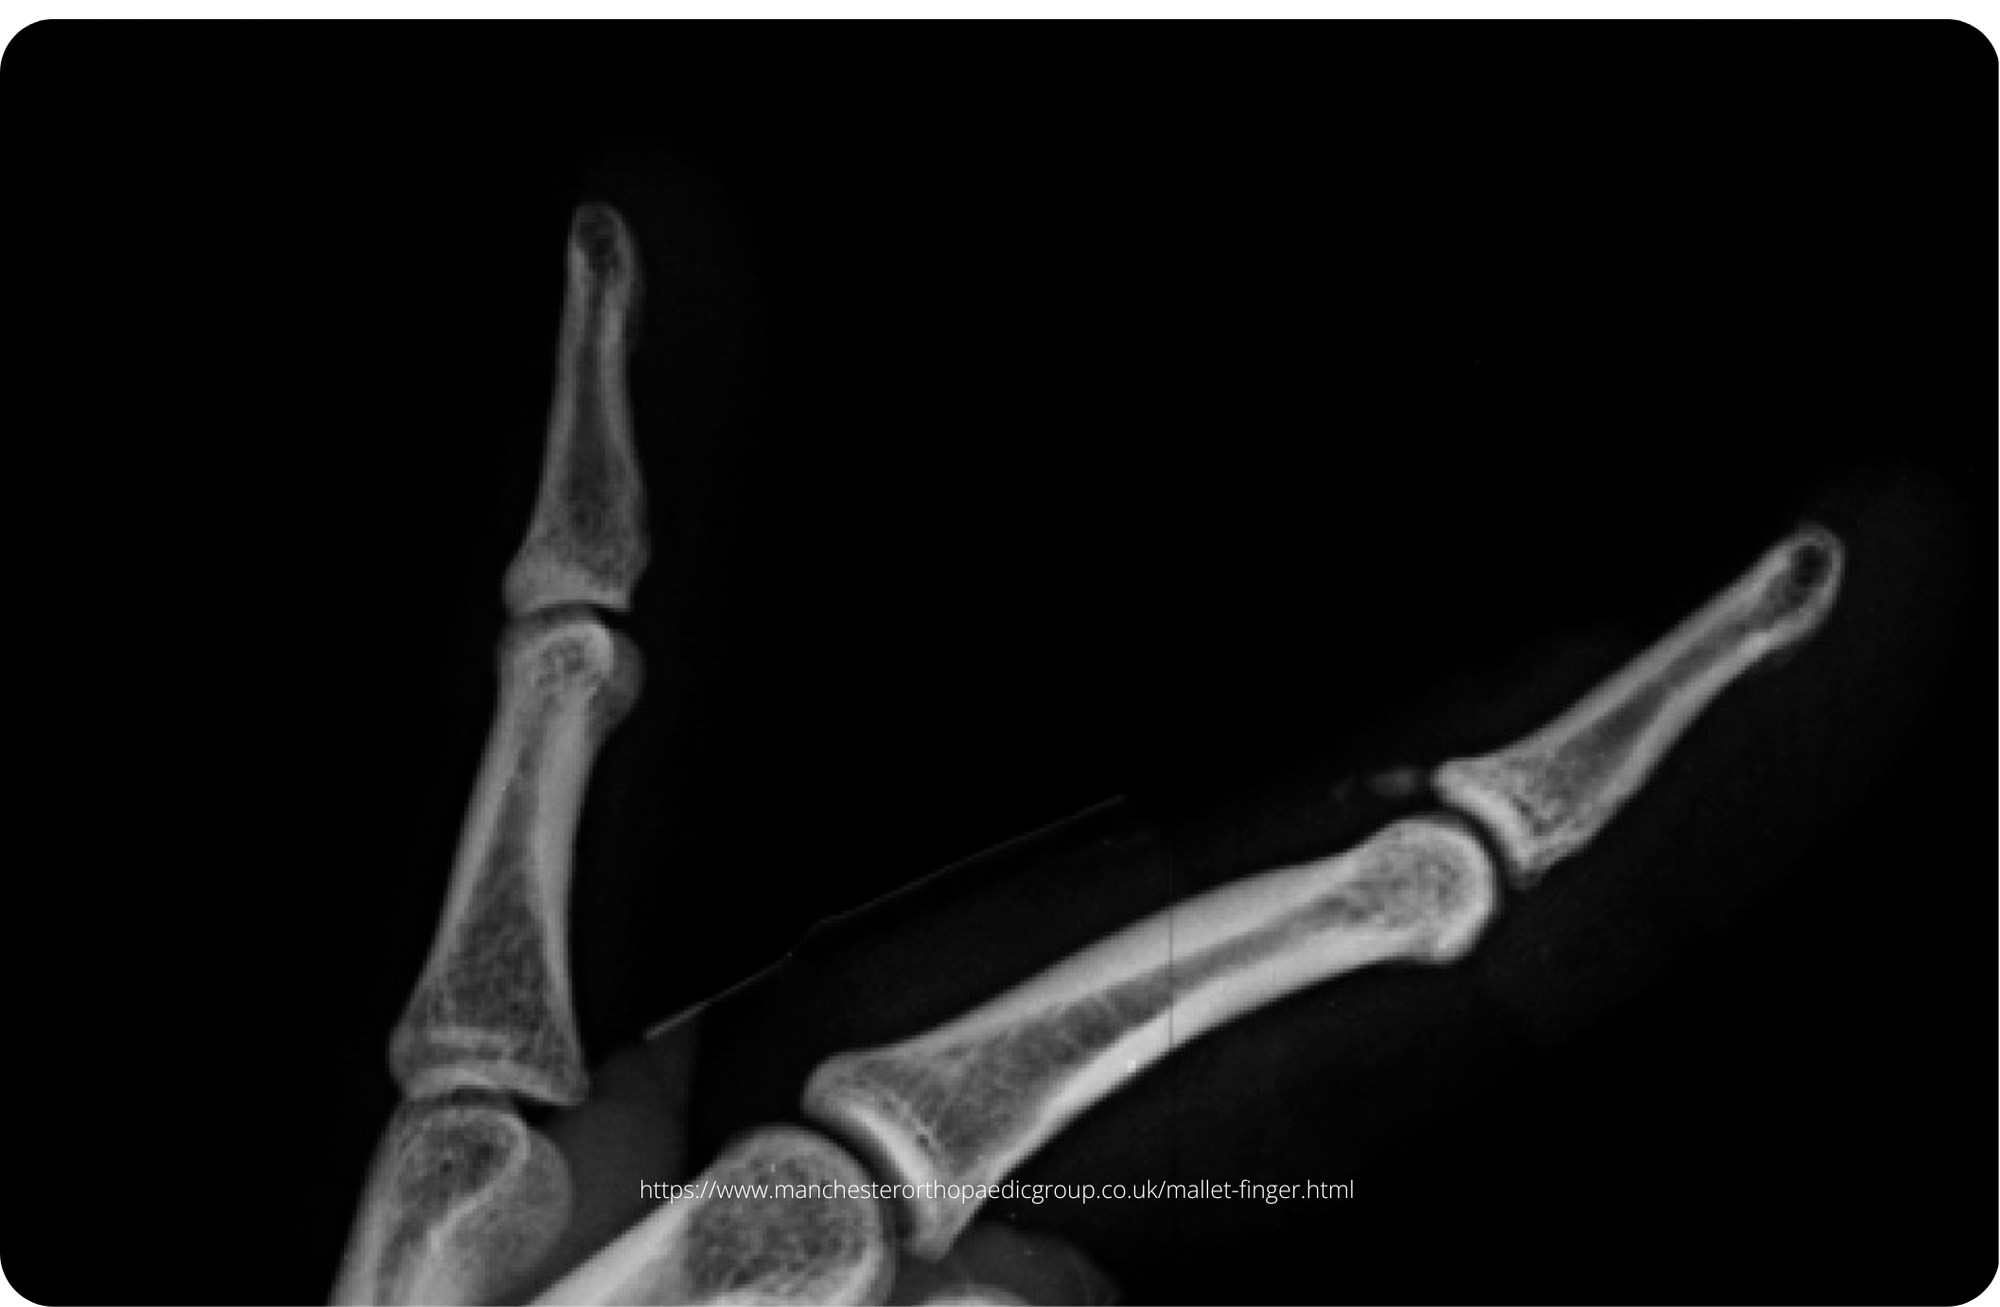

A patient with a mallet finger injury is unable to extend his fingertip. X-rays show a small bony avulsion fragment. This is a closed, bony mallet injury classified as Doyle Type I. Management includes continuous splinting of the DIP joint in extension for 6–8 weeks.

A 67-year-old man presents with mild pain and inability to extend the tip of his middle finger after trapping it in a car door. The injury mechanism was low energy, leading to a closed mallet deformity. The patient has a background of basal thumb steoarthritis but no other associated injuries.